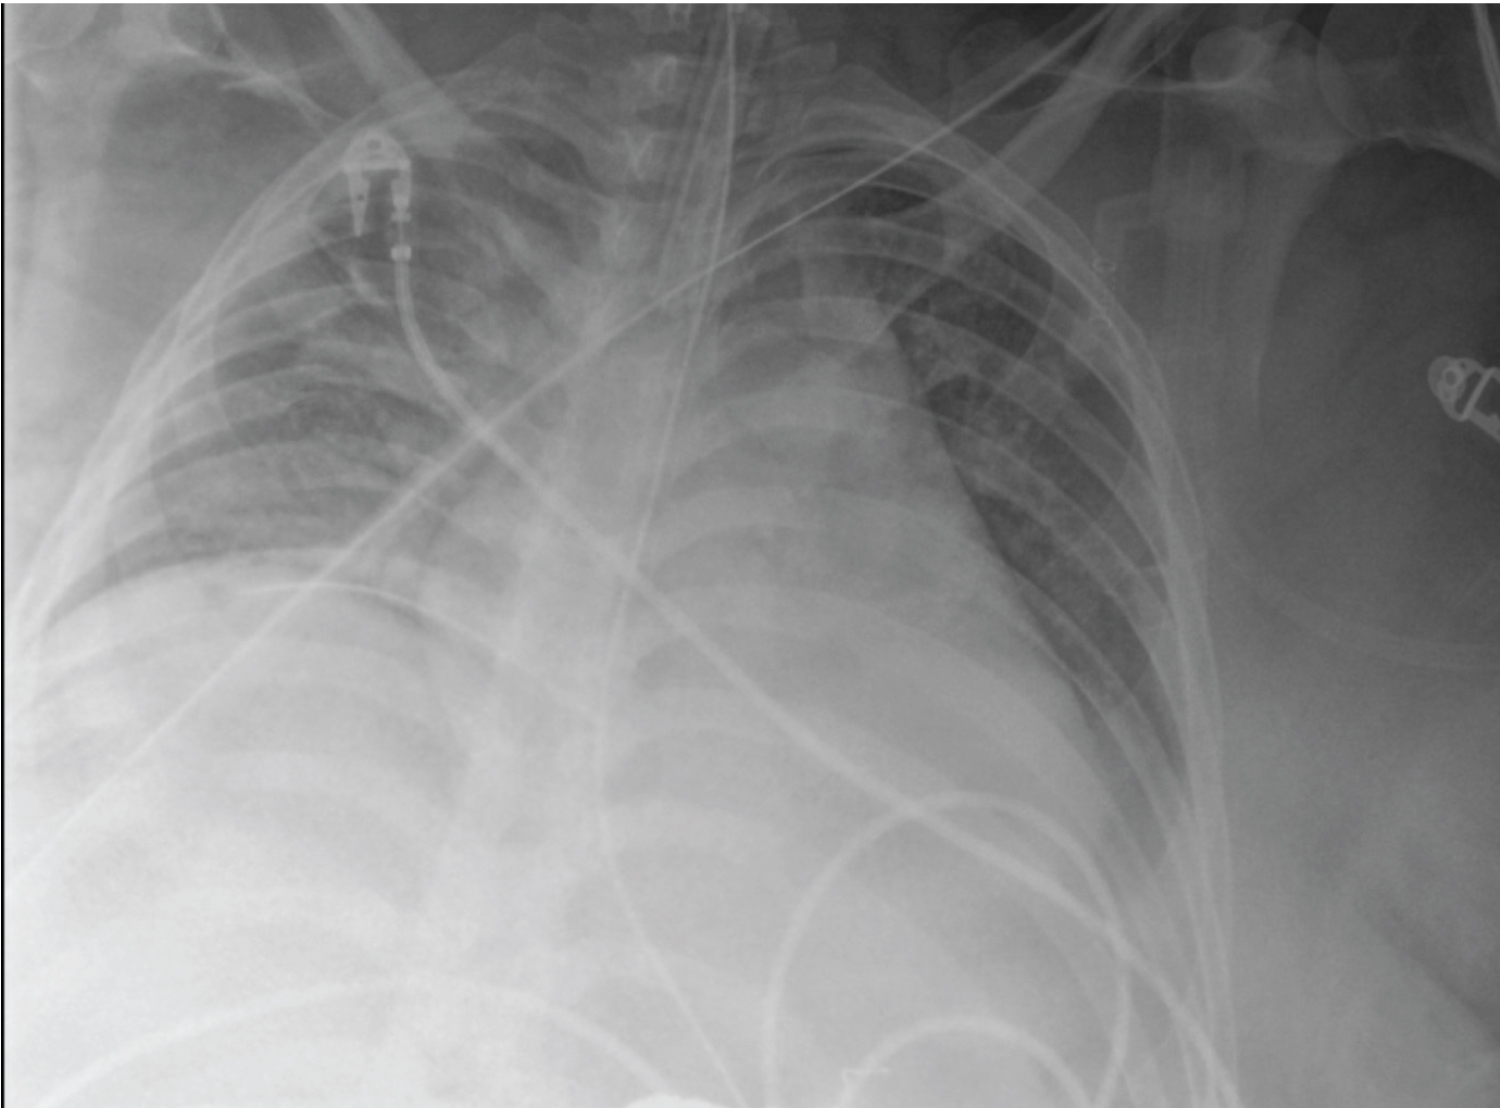

X-Ray eight hours later showed subcutaneous emphysema of the right chest wall (Figure 2A), with corresponding computed tomography (CT) showing worsening of the right-sided pneumothorax, as well as an intercostal pleurocutaneous fistula along the anterior superior chest wall (Figure 2B). A right-sided chest tube was then placed, and daily X-rays were performed to assess for resolution of the fistula (Figure 3). Within 12 hours improvement was seen, and within 36 hours the subcutaneous emphysema was nearly resolved (Figure 4).

Figure 2a: Portable Chest X-ray taken immediately after chest tube placement shows the extent of the right-sided subcutaneous emphysema.